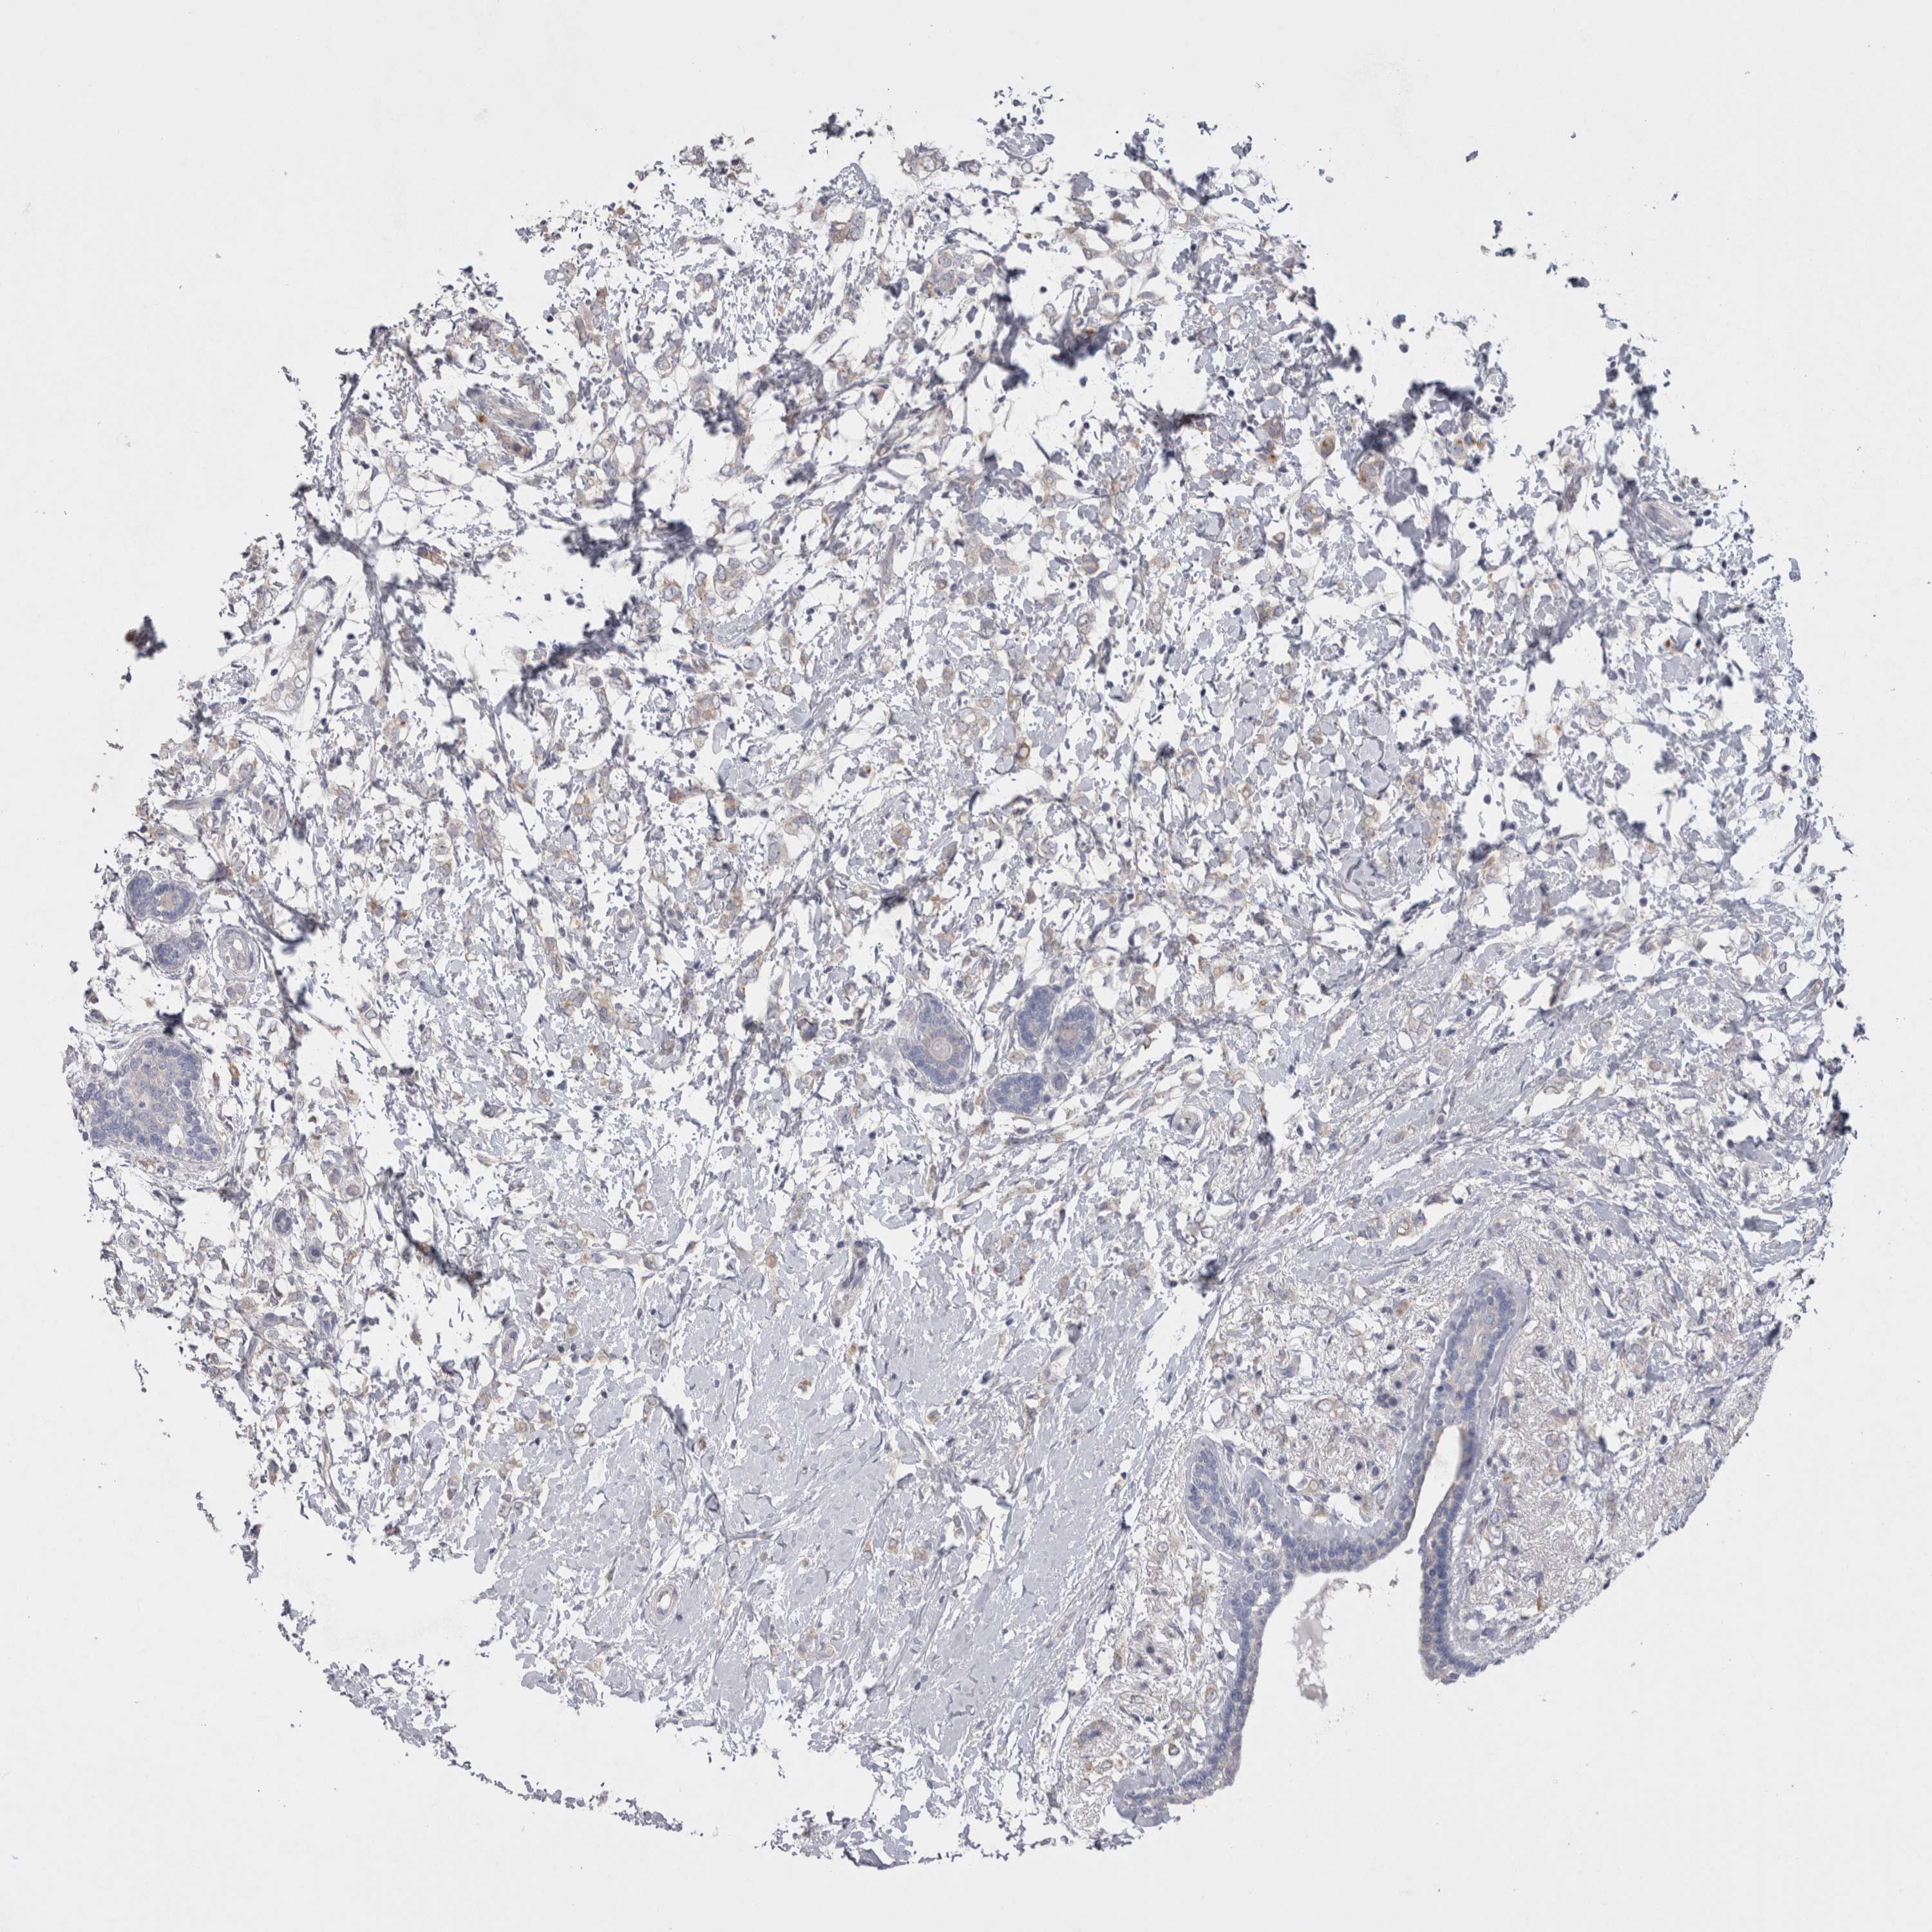

CANCER BREAST CANCER Show tissue menu

BRCA TCGA BRCA VALIDATION PROTEIN EXPRESSION